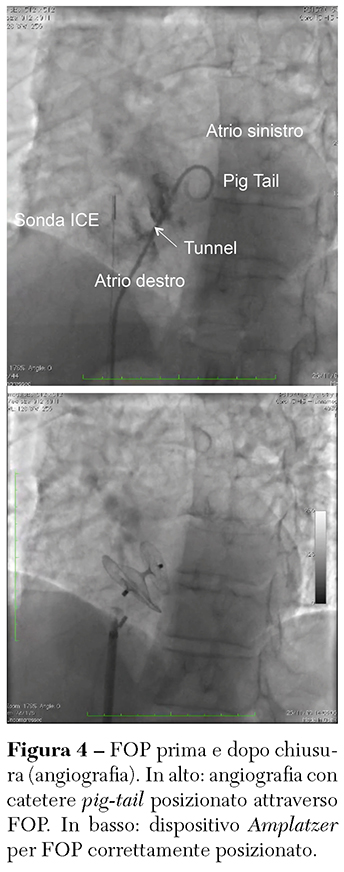

L’intervento si esegue in sala di Emodinamica (prevede quindi esposizione ai raggi X), mediante accesso percutaneo da una vena femorale, dal quale vengono inseriti gli strumenti per attraversare il FOP e, successivamente, il dispositivo di chiusura. Nel nostro laboratorio l’intervento è realizzato in anestesia locale, con monitoraggio del posizionamento del dispositivo attraverso un’apposita sonda ecografica intracardiaca, introdotta dalla vena femorale controlaterale. In alternativa, l’intervento può essere fatto in anestesia generale utilizzando un monitoraggio ecocardiografico trans-esofageo. Il posizionamento e il rilascio del dispositivo avvengono seguendo criteri specifici di corretto impianto e stabilità. L’intervento ha una durata media complessiva (ingresso-uscita di sala) di circa un’ora. Il ricovero successivo all’intervento prevede in genere una sola notte in ospedale, con dimissione a domicilio il giorno seguente, in terapia con due anti-piastrinici (aspirina e clopidogrel) per 4 settimane. La prosecuzione di aspirina sine die è decisa caso per caso in sede di rivalutazione al follow-up sempre a opera dell’Heart-Brain Team (Figura 4).